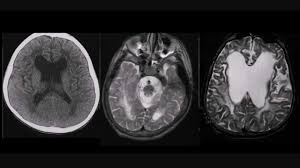

Các tổn thương chất trắng có thể được nhìn thấy bằng chụp cộng hưởng từ (MRI) với hình ảnh những điểm sáng trong não của bạn. Một số tổn thương chất trắng nếu nhỏ có thể không gây ra triệu chứng đáng chú ý. Nếu nhiều tổn thương chất trắng hơn sẽ biểu hiện nhiều triệu chứng hơn.

Chụp cộng hưởng từ (MRI): Chụp MRI giúp bác sĩ nhìn thấy mức độ tổn thương chất trắng trong não của bạn và phát hiện các bất thường khác nếu có như khối u, xuất huyết não, nhồi máu não.

Chụp cắt lớp vi tính (CT scan): Nếu như cơ sở y tế không đủ thiết bị chụp MRI, bác sĩ có thể chỉ định chụp CT. Tuy nhiên, MRI có chất lượng hình ảnh và độ nhạy tốt nhất để chẩn đoán bệnh thoái hóa chất trắng.

Chụp MRI có thể giúp bác sĩ chẩn đoán thoái hóa chất trắng